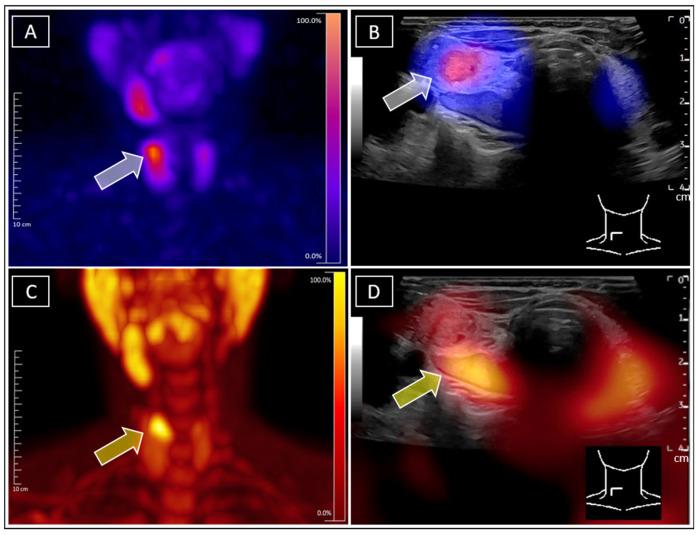

Simultaneous Identification of Tc-99m-Sestamibi-Positive Autonomous Thyroid Adenoma and Adjacent F-18-Ethylcholine-Positive Parathyroid Adenoma in Patient with Graves' Disease Using Real-Time Ultrasound Fusion Imaging.

A 49-year-old female presented for nuclear medicine diagnostics of a sonographically suspected parathyroid adenoma dorsal to the cranial pole of the right thyroid lobe. The patient received Tc-99m-pertechnetate and Tc-99m-sestamibi (including SPECT/CT) scans, revealing no sestamibi uptake by the suspected parathyroid adenoma but a ventrally adjacent autonomous thyroid adenoma. Additional F-18-ethylcholine-PET/CT as well as subsequent Tc-99m-sestamibi-SPECT/US and F-18-ethylcholine-PET/US fusion imaging confirmed the suspected diagnosis of simultaneous autonomous thyroid adenoma and parathyroid adenoma. A blood analysis showed additional Graves' disease.